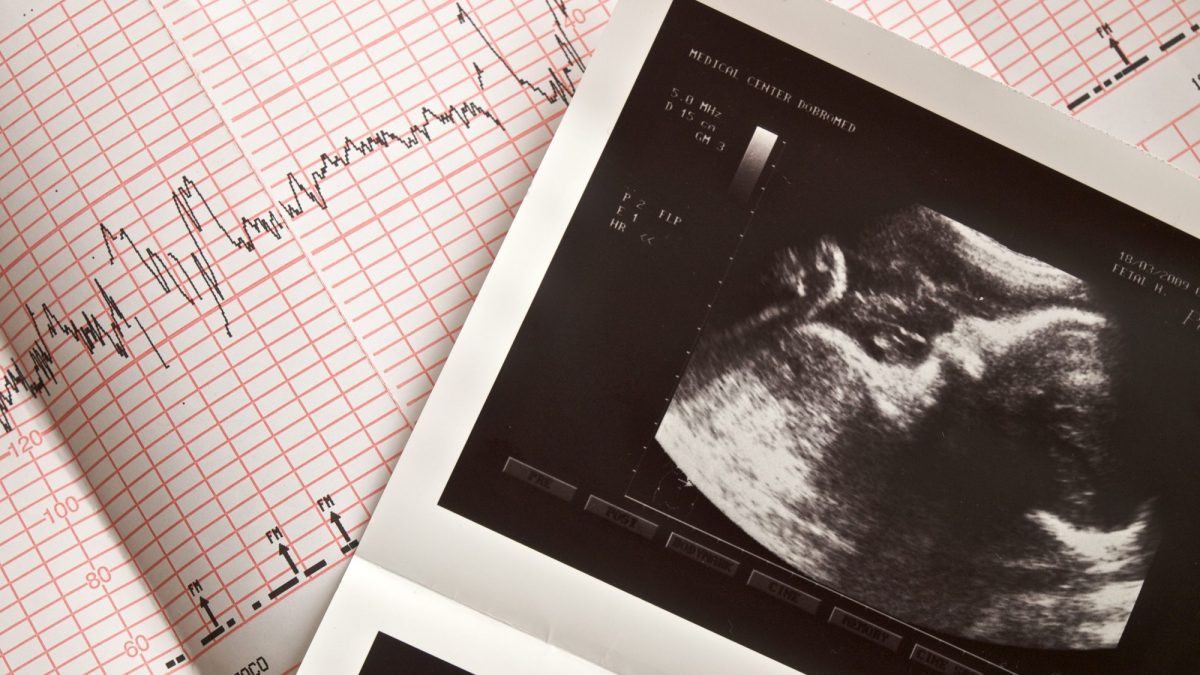

Dalla sesta settimana, in particolare, tramite una ecografia transvaginale, in grado di cogliere gli ultrasuoni, sarà possibile vedere e non sentire il battito del bambino, grazie ad un'immagine ecografica. È attorno alla decima settimana che invece il cuore del bambino sarà anche udibile nello studio del ginecologo. Durante il secondo trimestre, in particolare tra la diciannovesima e la ventunesima settimana di gravidanza, si può studiare l'anatomia del cuore e sentire il battito attraverso l'ecografia morfologica, che permette di vedere il cuoricino contrarsi ed espandersi.

L'auscultazione del battito cardiaco fetale è uno dei parametri più significativi per valutare il benessere del feto. Durante il travaglio di parto, però, non sarà più l'ecografia a fornire i feedback necessari al personale sanitario ma la cardiotocografia.

Mediante due sonde esterne, cioè, vengono valutate contemporaneamente la frequenza cardiaca fetale e le contrazioni materne: la registrazione di questo tracciato permette di conoscere in tempo reale lo stato di benessere del feto e consente ad ostetriche e ginecologi di prendere le giuste decisioni in prossimità del parto.